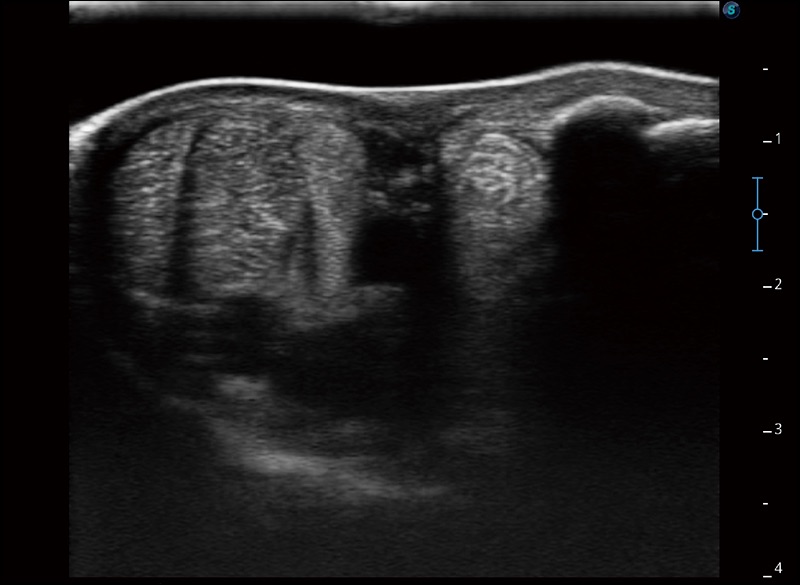

临床图